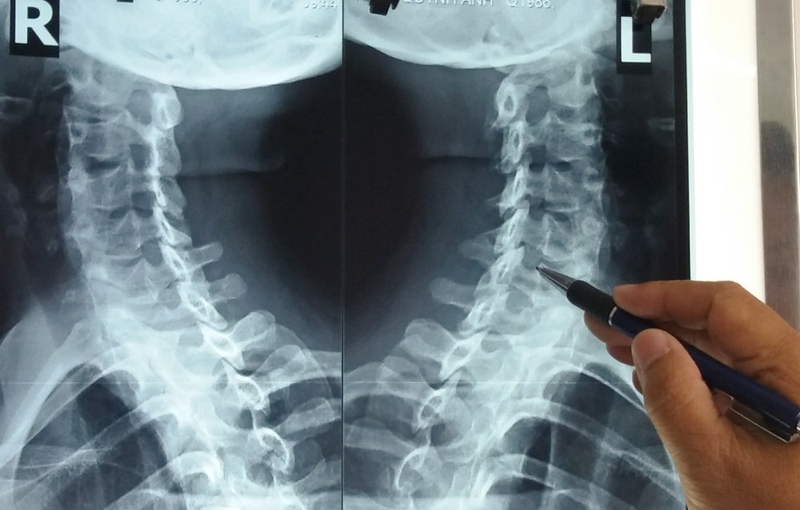

Chụp X quang gai cột sống là việc ứng dụng kỹ thuật máy chụp X quang chuyên dụng lên bệnh nhân. Máy chụp X quang phát chùm tia X ra để phản chiếu hình ảnh đốt sống có gai của bệnh nhân lên phim chụp. Tia X này khi đi qua cơ thể sẽ chỉ phản chiếu hình ảnh màu trắng với hệ xương khớp, còn các cơ quan khác thì có màu xám đen. Việc bệnh nhân chụp X quang gai cột sống sẽ cho ra được hình ảnh rõ nét về các bất thường, về các bệnh lý liên quan đến xương khớp như là bệnh gai cột sống, thoát vị đĩa đệm,… Tùy vào góc chụp và vị trí chụp cột sống mà cho ra kết quả khác nhau.

Phim chụp X quang gai cột sống sẽ giúp bác sĩ có đánh giá chính xác và chẩn đoán được bệnh, đồng thời xác định được vị trí bệnh nhân bị gai cột sống, tình trạng phát triển của gai hiện tại, mức độ bệnh nặng nhẹ. Sau đó tùy vào từng trường hợp mà bác sĩ sẽ đưa ra phác đồ điều trị bệnh gai cột sống phù hợp.

Nên chụp X quang gai cột sống khi nào và phải chuẩn bị những gì 3Các gai xương sẽ hiển thị hết sức rõ ràng trên phim chụp.